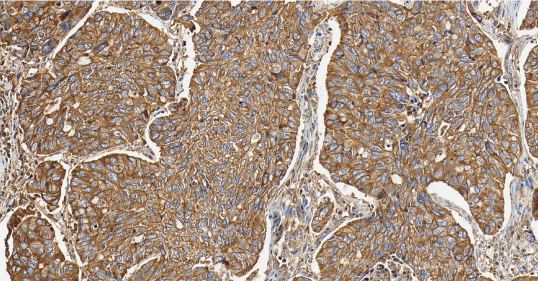

TTF-1

TTF-1——甲状腺转录因子-1,属于 NKX2 转录因子家族。

• 定位:细胞核。

• 功能:TTF-1 是调控肺组织和甲状腺器官特异性基因表达的核转录因子,对肺泡上皮细胞的终末分化和表面活性物质的分泌至关重要。

TTF-1 是关键的核转录因子,表达具有高度组织特异性。它在肺腺癌和甲状腺癌中高表达,是诊断这些原发癌的核心标志物[3]。其临床价值在于鉴别转移癌的原发部位:若 TTF-1 阳性,强烈提示肿瘤来源于肺或甲状腺。值得注意的是,肺鳞癌中 TTF-1 通常为阴性,需结合其他标志物来进一步确认。

图 2.人肺癌组织的 TTF-1 免疫组化分析。